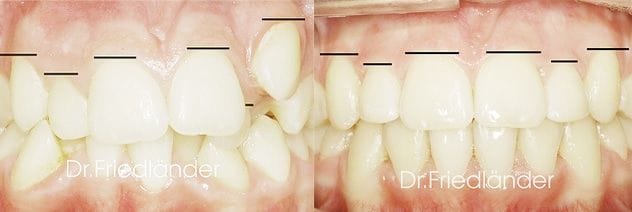

Cada margen de cada diente tiene que tener su altura, asi los margenes de los incisivos centrales (linea verde en la imagen) tienen que estar a la misma altura de los caninos (linea negra en la imagen) y 0.5mm aproximadamente mas alto que el margen del incisivo lateral (linea azul).

Nivelacion de margenes gingivales

Es facil darse cuenta de la impresionante mejora de la estetica cuando los margenes estan nivelados. (aun sin tratamiento de estetica)